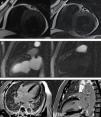

A 63‐year‐old man was admitted for non‐ST‐elevation myocardial infarction. Echocardiography showed preserved biventricular systolic function with apical hypokinesia. Apical 4‐chamber color Doppler view revealed abnormal diastolic flow, apparently intramyocardial (Figure 1A and Video 1). Coronary angiography revealed moderate (60%) coronary stenosis in the mid right coronary artery (Figure 1B), with a fractional flow reserve of 0.91, compatible with a functionally non‐significant lesion. Multiple small fistulae originating from both the right and left coronary arteries were observed, draining into the left ventricle (Figure 1B and C and Videos 2 and 3). Cardiac magnetic resonance imaging (MRI) provided further characterization of these fistulae, which were visible in T2‐weighted sequences in short axis view in the anterior and posterior interventricular grooves (Figure 2A). First‐pass myocardial rest perfusion imaging in two‐chamber view revealed epicardial hyperenhancement of the anterior wall simultaneous with aortic opacification (Figure 2B and Video 4), as well as earlier perfusion of the mid and apical anterior segments. There was subendocardial late gadolinium enhancement (LGE) in the apical inferior segment, compatible with non‐transmural myocardial infarction (Figure 2C). Dobutamine stress echocardiography under optimized therapy showed no inducible ischemia and the patient was discharged, and has remained stable ever since, now at two‐year follow‐up.

(A) Two‐dimensional echocardiography in 4‐chamber color Doppler view showing abnormal intramyocardial diastolic flow in the apical lateral segment (arrow); (B) selective right coronary angiography showing 60% stenosis in the mid right coronary artery and multiple coronary fistulae arising from its distal segment and draining into the left ventricle (arrow); (C) selective left coronary angiography showing multiple coronary fistulae arising from the distal segments of the left coronary artery, also draining into the left ventricular cavity (arrow).